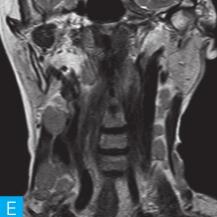

喉咽部MRI检查:病人采取仰卧位,横断位扫描为主,包括T1WI、T2WI及T2WI脂肪抑制序列,扫描范围自鼻咽部至喉咽以下,扫描层厚为3.5mm、层间隔0.35mm,矩阵512×512;辅以冠状位T2WI,矢状位T2WI序列及脂肪抑制序列,平扫后行横断位、冠状位及矢状位的增强扫描,造影剂量0.2ml/kg。见图1。

图1 咽喉部MRI:A.喉咽部MR横断面平扫T1WI;B.喉咽部MR横断面T2WI;C.喉咽部MR横断面T2压脂;D.喉咽部MR横断面增强T1WI;E.喉咽部MR冠状面T2WI;F.咽喉部MR冠状面增强T1WI

MRI平扫可见右侧扁桃体较大的软组织肿块,T1WI呈稍低信号,T2WI呈稍高信号,信号较均匀,T2WI压脂序列上呈高信号,病变与右侧咽扁桃体及舌根部分界不清,左侧咽扁桃体肿大,口咽腔明显变形狭窄,病灶延伸至喉前庭;双侧锁骨上窝及颈血管鞘周围间隙内可见多发大小不等的肿大淋巴结,大部分肿大淋巴结信号较均匀,呈稍高信号,边界清楚,右侧颈部间隙内个别肿大淋巴结内见少量斑片状液化坏死区;增强扫描后下咽部病变及双侧颈部间隙内的肿大淋巴结均呈明显的较均匀强化,提示该两处占位病变的血供较为丰富,且可能为同源性病变,因此采取“一元论”诊断思维进行分析更为合理。

(1)发现病变与认证:扁桃体及颈部病变较为容易发现,主要是分析两方面:一是仔细观察咽部有无原发病变,原发病变的形态及信号;二是评价淋巴结的分布,淋巴结的信号及生长特点。本病例基本征象为扁桃体病变信号均匀,无坏死,颈部淋巴结分布广泛,信号均匀。

(2)定位诊断:对于本病例来说,发现两处病变,包括咽部和颈部。咽部的病变位于扁桃体,延伸至喉咽腔,口咽腔和梨状窝受压变窄。颈部的病变为多发淋巴结增大,淋巴结广泛分布于Ⅱ~Ⅴ区。

本病例的特点为右侧扁桃体肿块,病变边界较清楚,表面光滑,信号均匀。双侧颈部间隙内多发肿大淋巴结,淋巴结围绕颈动脉鞘,部分病变融合倾向,广泛分布于Ⅱ~Ⅴ区,增强后病变较明显强化。

该病例首先对病变进行定位,包括咽部的和颈部的。咽部的病变:病变位于扁桃体,延伸至喉咽腔,口咽腔和梨状窝受压变窄(引起异物感和吞咽困难的原因)。颈部的病变:多发淋巴结增大,淋巴结广泛分布于Ⅱ~Ⅴ区。扁桃体病变的信号特征:扁桃体病变表面光滑,提示黏膜完整,病变来源于黏膜下,病变信号均匀,无坏死,进一步支持病变来源于黏膜下。颈部淋巴结病变的特征:淋巴结分布广泛,信号均匀(可以初步排除结核和转移,后两者容易坏死),围绕颈动脉鞘,但是不侵犯颈动脉鞘(转移容易侵犯颈动脉鞘),部分淋巴结融合倾向(结核淋巴结增大,无融合倾向,而且容易坏死),病变中度强化,进一步支持颈部淋巴瘤的诊断。诊断原则:首先仔细观察咽部有无原发病变,原发病变的形态及信号,尤其黏膜是否完整。其次评价淋巴结的分布,淋巴结的信号及生长特点。